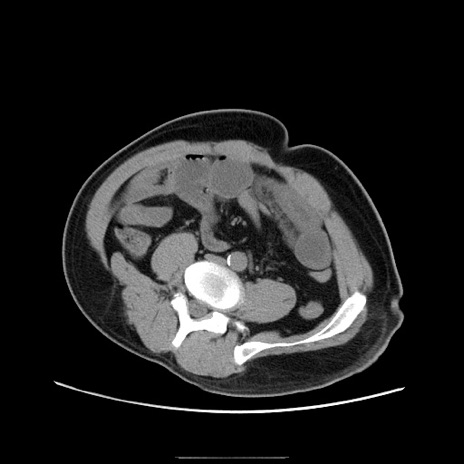

冠状断像

【症例】50歳代男性

【主訴】腹痛

【現病歴】AVMからの被殻出血のため回復期リハ病棟入院中。 本日午後3時頃急に下腹部痛が出現した。

【既往歴】AVM、被殻出血、虫垂炎、高血圧

【身体所見】意識晴明、左半身不全麻痺、会話の理解は良好、36.5°C、腹部:膨隆、全体に板状硬、下腹部正中に圧痛点あり、反跳痛-、筋性防御不明、右下腹部にope scar

【データ】WBC 9400、CRP 0.06